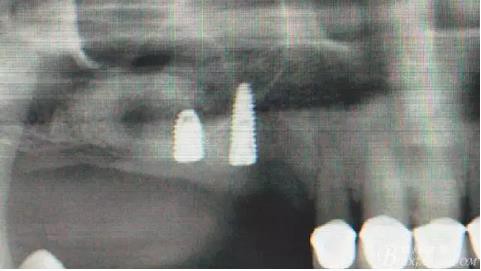

術后X光片。